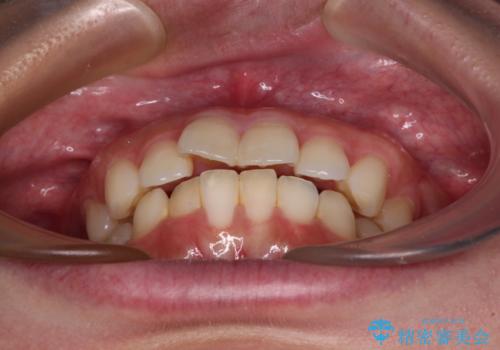

- 全体的なデコボコと口元の突出感を改善したいとのことで来院された患者様です。

このままデコボコを整えるとさらに突出感が増すため、上下左右の第一小臼歯を抜歯し、ワイヤー装置にて矯正しました。